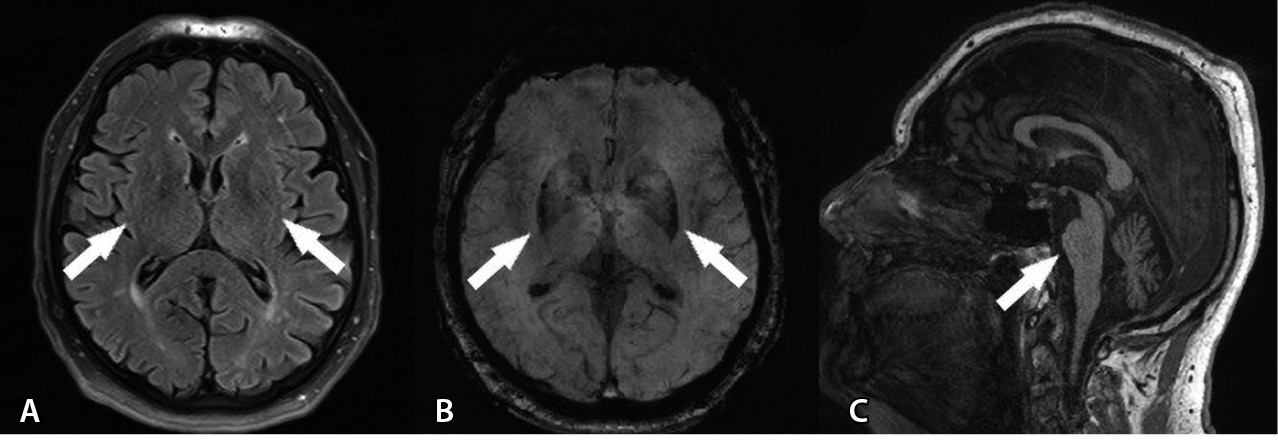

Проведены следующие дополнительные методы исследования. При УЗИ остаточной мочи ее объем составил 105 мл. На магнитно-резонансной томограмме (МРТ) головного мозга – признаки атрофии ствола мозга в режиме Т1, в режиме T2-FLAIR – симптом «креста» (рис. 1).

Рис. 1. Магнитно-резонансная томография головного мозга пациента В. А – Т1-взвешенное изображение, сагиттальный срез: признаки атрофии варолиева моста в виде уплощения его основания, а также расширение борозд мозжечка. Б, В – Т2-FLAIR, Т2-взвешенное изображение, аксиальные срезы: симптом «креста», или “hot cross bun”: гиперинтенсивность волокон мосто-мозжечковых путей и ядер шва (отмечено кругом)

На основании вышеуказанного, согласно критериям диагностики МСА от 2022 г., пациенту В. был выставлен клинический диагноз достоверной МСА-М.